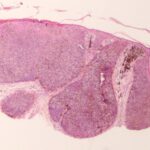

melanoacanthoma